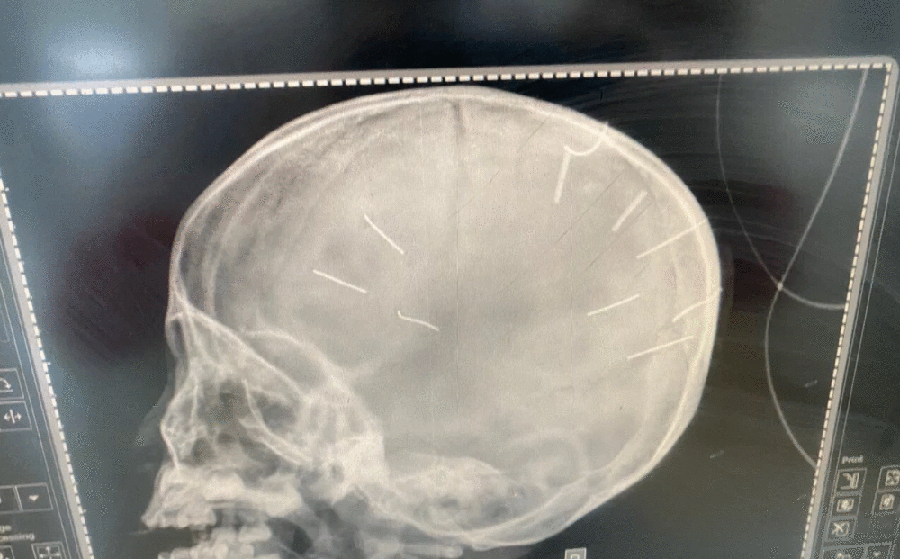

Cháu bé 3 tuổi có nhiều vật giống đinh ghim vào đầu đang nguy kịch